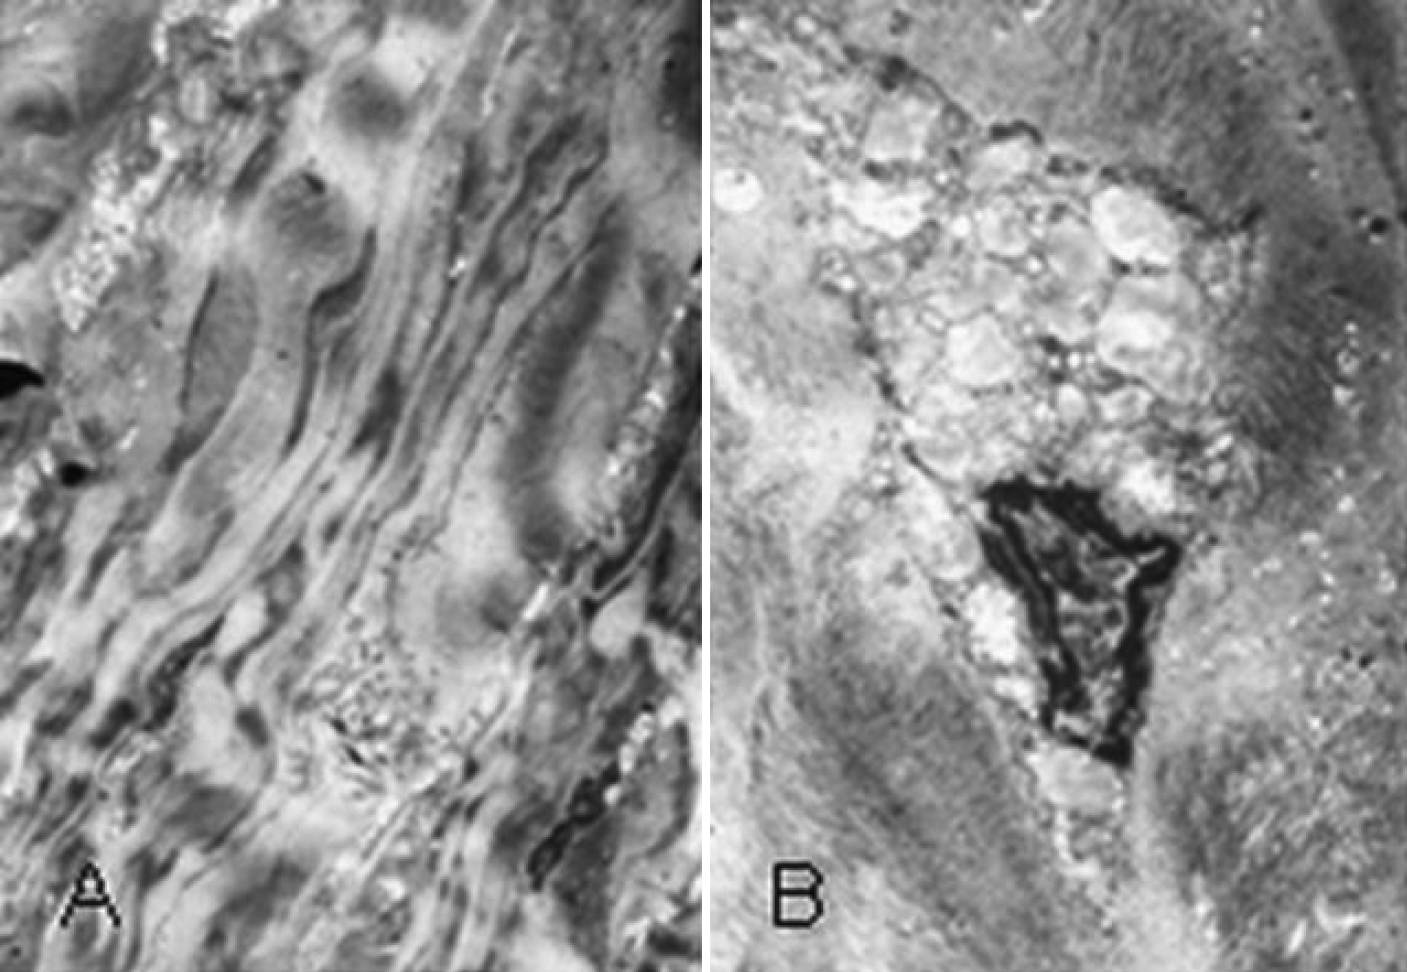

Figure 4. Transmission electron microscopy result of paraffin section of the proband’s cornea stained with Hale's colloidal iron. A: The picture shows that the collagen fibers in the corneal stroma are irregular, enlarged, and intensive (1,500X). B: The picture shows hyperplastic, active fibroblasts and intracytoplasmic vacuoles in the cornea (5,000X).